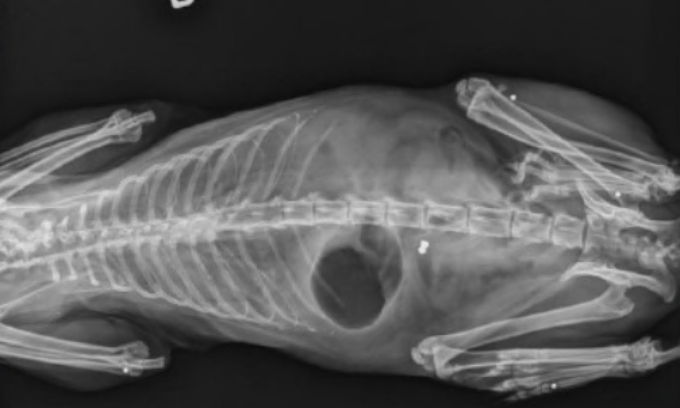

La volontaria si è anche accorta di alcuni segni sul corpo. Lo ha quindi preso e subito portato dal veterinario. E’ bastata una radiografia per scoprire che Jerry aveva in corpo, all’altezza del petto, un piccolo proiettile e altri piombini nelle zampe. Chi ha sparato, quindi, lo ha fatto più volte e con il preciso intento di uccidere. Il medico ha tentato di tutto per salvarlo ma dopo cinque giorni di agonia il gatto è morto.